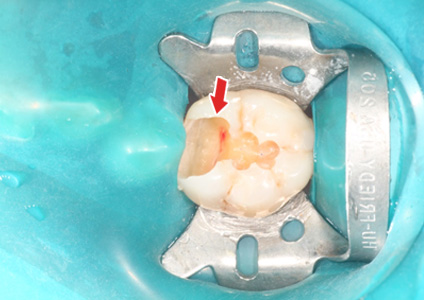

ÃæÄ¡Ä¡·á Áß¿¡ Ä¡¼ö°¡ ³ëÃâµÈ ¸ð½À - 2